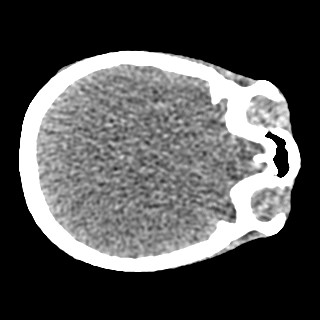

Cone-beam CT (CBCT) employs a flat-panel detector to achieve three-dimensional imaging with high spatial resolution. However, CBCT is susceptible to scatter during data acquisition, which introduces CT value bias and reduced tissue contrast in the reconstructed images, ultimately degrading diagnostic accuracy. To address this issue, we propose a deep learning-based scatter artifact correction method inspired by physical prior knowledge. Leveraging the fact that the observed point scatter probability density distribution exhibits rotational symmetry in the projection domain. The method uses Gaussian Radial Basis Functions (RBF) to model the point scatter function and embeds it into the Kolmogorov-Arnold Networks (KAN) layer, which provides efficient nonlinear mapping capabilities for learning high-dimensional scatter features. By incorporating the physical characteristics of the scattered photon distribution together with the complex function mapping capacity of KAN, the model improves its ability to accurately represent scatter. The effectiveness of the method is validated through both synthetic and real-scan experiments. Experimental results show that the model can effectively correct the scatter artifacts in the reconstructed images and is superior to the current methods in terms of quantitative metrics.